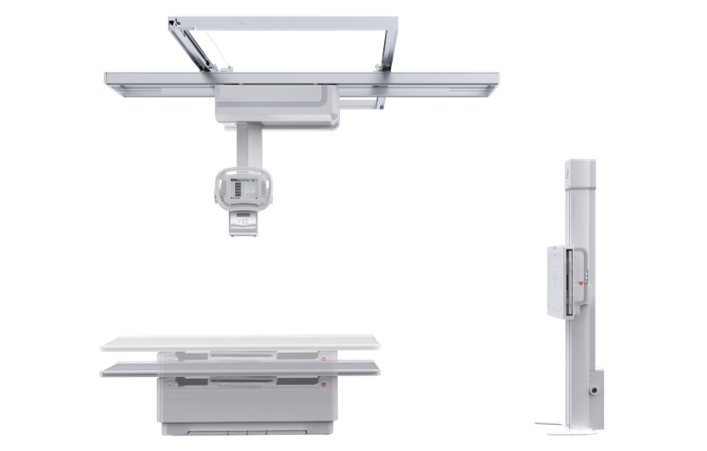

PLD7600

多功能懸吊動態DR

一機多用 PLD7600

一機多用 PLD7600

● 智能升降床體

智能升降床設計,便于老、幼、病殘或行動不便者上下床,給患者以及醫護人員帶來更舒適的檢查體驗,智能化程度極高。

● 雙向自動跟蹤

探測器與球管雙向自動跟蹤,無需手動校正,多角度高精度實時同步;

胸片位、床上位電動轉換,一鍵到位。

● 低位攝影

球管及胸片架可大范圍縱向移動,平板探測器中心最低離地35cm,輕松滿足膝關節、踝關節等低位攝影的要求。

● 特殊角度攝影

牛頭可全角度旋轉,滿足全身各部位的應用,特有的傾斜投照位,可滿足特殊病人的臨床應用。

● 手動電動一體化

懸吊配備手動模式與電動模式,沿天軌橫縱移動時可選手動或電動,滿足不同醫護人員使用習慣。

● 自動對中

球管自動對準探測器中心點,無需手動校準,便捷高效。

● 自動控制曝光

無需手動調節,系統準確地控制射線劑量,獲得適當的感光量,保證優秀的影像效果。

● 圖像拼接

系統可以識別曝光圖像,無需設置識別點即完成精準拼接,呈現大范圍完整影像。

● 平板在線充電技術

胸片架或攝影床的片盒系統內置在線充電口,快速充電,持久續航。